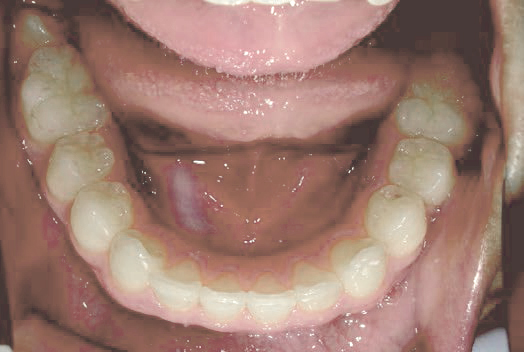

Before

After

歯がガタガタに並んでいて、前歯の真ん中の位置が少し左にずれていました。

奥歯が生えるためのスペースが足りず、永久歯が生えて来られない状況が確認できました。

また、飲み込むとき下くちびるに力が入ってしまうクセが見られ、お顔全体の成長が遅れている様子が確認できました。

治療を終えて

歯がきれいに生えるためのスペースをしっかり確保することができ、歯並びを乱していたお口のクセも改善されたため、奥歯が生えるスペースを確保することができました。

しっかり噛めるかみ合わせを作ることが、将来の健康につながるので「よく噛む」練習も続けてもらっています。

主訴・治療内容 歯がガタガタになってきたことに悩み、無料相談に来院されました。

治療期間 3年

費用 462,000円(税込)